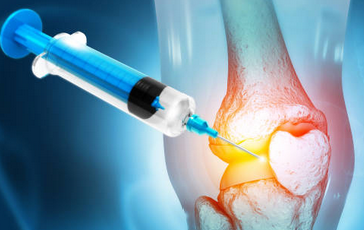

무릎 연골 찢어짐은 무릎 관절에 있는 연골이 손상되거나 파열되는 상태를 말합니다. 무릎 연골 찢어짐의 원인은 다양하지만, 대표적으로는 무릎에 직접적인 충격이 가해지거나, 무릎을 비틀거나 꺾는 동작을 반복하거나, 과체중이나 통풍 등으로 인해 무릎에 과도한 부하가 가해지는 경우가 있습니다 . 무릎 연골 찢어짐의 증상은 무릎에 통증이나 부종이 생기고, 무릎을 굽히거나 펴는 것이 어렵고, 무릎을 움직일 때 뚝뚝 소리가 나는 경우가 있습니다 . 무릎 연골 찢어짐의 치료방법은 손상의 정도와 위치에 따라 다르지만, 일반적으로는 약물 치료, 연골 강화 주사, 수술 등이 있습니다 . 약물 치료는 증상이 심하지 않을 경우에 염증을 줄이고 통증을 완화하기 위해 사용되며, 연골 강화 주사는 약물로 치료가 안될 경우에 연골을 보호하고 재생시키기 위해 사용됩니다. 수술은 연골 손상이 심하거나 많이 찢어졌다면 필요한 경우로, 찢어진 부위를 절제하거나 봉합하거나 타인의 연골판을 이식하는 방법이 있습니다 .

무릎 연골 찢어짐의 치료는 손상의 정도와 환자의 상태에 따라 다릅니다. 약물 치료, 물리 치료, 수술 치료 등이 있습니다. 약물 치료는 통증과 염증을 줄여주는 약을 복용하는 방법입니다. 물리 치료는 무릎 관절의 움직임과 근력을 회복하기 위해 운동이나 전기 자극 등을 하는 방법입니다. 수술 치료는 손상된 연골을 절제하거나 이식하는 방법입니다.

수술 치료는 보통 관절경 수술로 이루어집니다. 관절경 수술은 무릎에 작은 구멍을 뚫고 관절경이라는 카메라와 작은 기구를 넣어서 수술하는 방법입니다. 수술 방법에 따라 절제술과 이식술로 나뉩니다. 절제술은 손상된 연골을 제거하는 방법이고, 이식술은 손상된 부위에 새로운 연골을 이식하는 방법입니다. 수술 비용은 수술 방법에 따라 달라지지만, 일반적인 절제술의 경우 200만 원에서 300만 원 내외입니다.